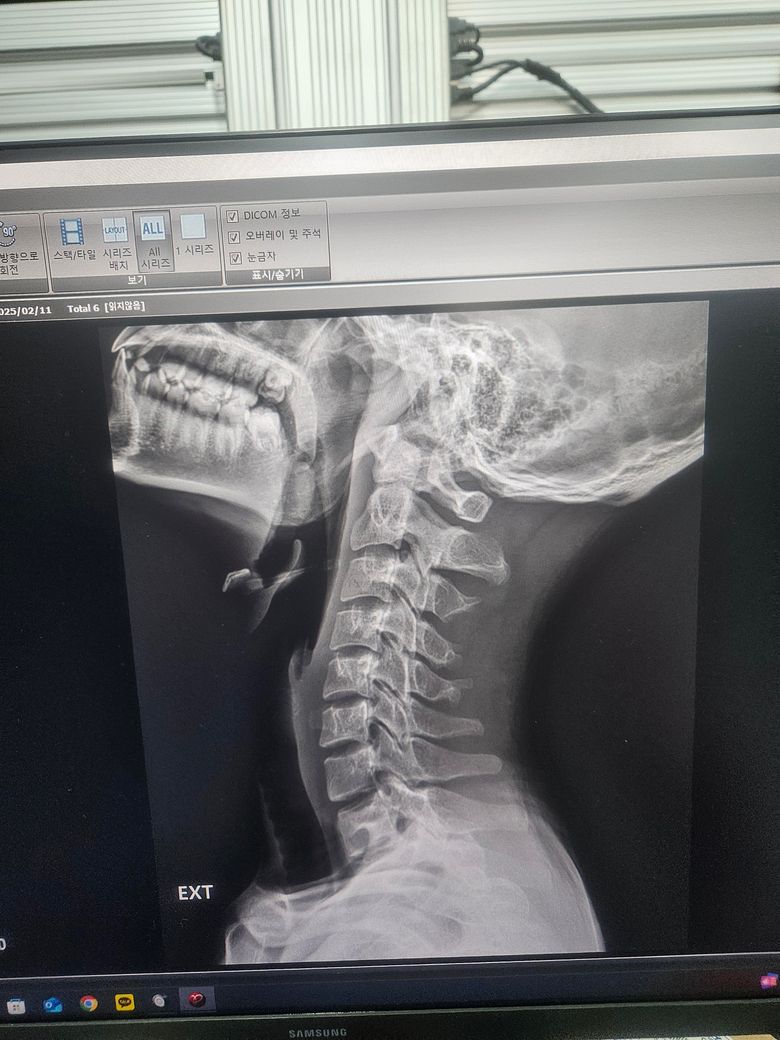

경추 불안정증인가요? 아시는분 제발 ㅜㅜ

몇번째 글 올리는건지 모르겠네요 경추 1번 과 2번 사이가 3mm미만이면 정상범위라는데 저는 몇미리인가요 불안정증이 있는건가요 ㅜㅜ

• 1번 째 사진

실제 영상을 보면서 측정을 해야 합니다

사진을 찍은 것으로는 측정이 되지 않습니다.

단순히 영상 사진을 다시 사진으로 찍은 자료만으론 판단 불가합니다. 세팅을 어떻게 했느냐에 따라 보이는 길이와 실제 길이가 차이가 나기 때문이죠. 사진을 다시 사진으로 찍으면서 생기는 오류도 있을수 있구요.

영상 찍은 병원 담당 의사에게 물어보는게 제일 정확합니다